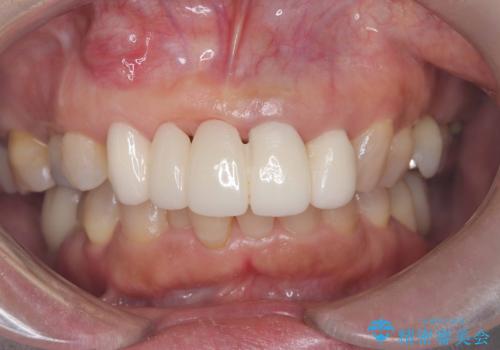

[ セラミック治療 ] 前歯の見た目を改善したい

担当医 大元洋佑